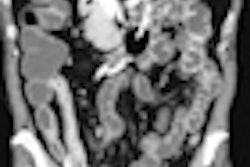

Care must be taken to compare views, delegates learned. Demonstrating this was a case in which abnormal bowel loops depicted in an axial view indicated something wrong but it was unclear exactly what. Coronal images showed a narrowing of a small-bowel loop causing obstruction, related to a postsurgical adhesion.

According to Curvo-Semedo, it was possible to differentiate two types of adhesion: obstructing and nonobstructing. Nonobstructing adhesions are harder to see on CT, he noted, pointing to the potential role of MRI in their detection. Obstructing adhesions, simple, closed loop, and strangulated were easy to detect and characterize by CT. Typical imaging findings for an adhesion included an abrupt narrowing of the small bowel.